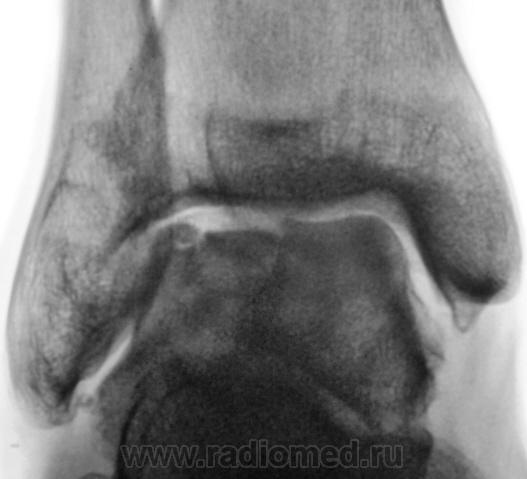

Пациент направлен на рентгенографию голеностопного сустава с диагнозом ДОА.

После внутрисуставного перелома вероятность доа оччень высока. Колгда была травма?

Травма была два года тому.

Похоже  на  остеохондропатию  блока  таранной  кости  +   ДОА.

А присутствует линейный (или лентовидный, я их путаю) остеопороз, а это признак острого процесса.

Игорь Иванович, спасибо за книжные выдержки (никогда (пока?) не видел лентовидного остеопороза; кстати, и в наблюдении - не вижу)!

Так, всё же как? Считаете, что здесь артрит или остеомиелит, ИЛИ же остеопоротическая перестройка - сама по себе?..

Только не последнее...

+ за лентовидный остеопроз...

С учётом стрелочек, надо полагать, остеомиелит!..

А я за "очаговый остеопоз сам по себе"!

Будем думать, что некроз блока таранной кости не такой уж и асептический, какая-то инхвекция там есть.

Посттравматический артроз с кистовидной перестройкойлатерального мыщелка Субхондральное уплотнение исужение суст. щелей естьИ неконгруэнтность большеберцового эпифиза к таранной маленько просматривается?